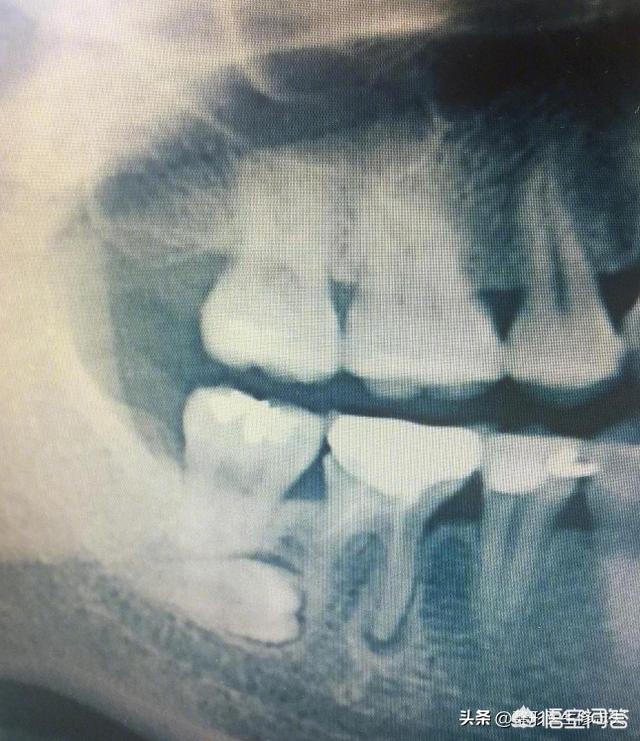

智齿生长在牙槽骨的末端,现现代人的牙槽骨因为食物越来越精细化,所以下颚骨在长度宽度等有不同程度的退化,也就导致没法提供智齿萌出的空间,这样可能造成智齿在萌出的位置、方向、高度上发生异常,所以也就容易出现健康问题,比如智齿难以清洁到容易滋生细菌、引发龋齿、牙冠损伤、牙齿不整齐等。

↓一颗横生的智齿

所以,如果长智齿或智齿出现问题了,一般建议到正规牙科进行拔除。